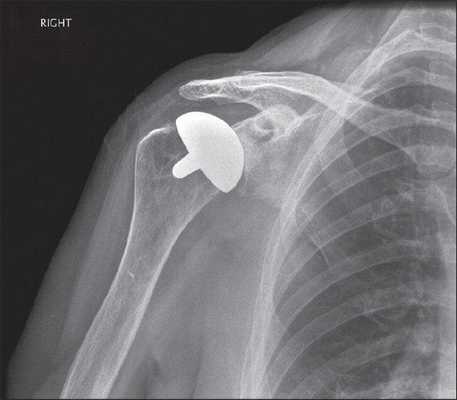

Артроз плечевого сустава на рентгене.

- Поверхностное. Применяется, когда минимальны повреждения головки кости пациента и много костной ткани можно сохранить. Головка обтачивается специальным инструментом, на нее «сажается» имплантат, замещающий собой поверхность сустава.